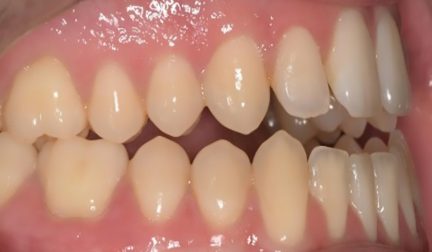

Classe III, béance, arcades étroites, arcades asymétriques, déviation médiane maxillaire, déviation médiane mandibulaire, décalage médian, encombrement, rotations, espacement, diastème

Mésialisation, courbe de Spee nivelée, égression, expansion, rétraction, vestibulo-version, fermeture de l'espace, traitement de phase II, élastiques : Classe III

- Relation de classe I obtenue

- Guidage fonctionnel des canines des deux côtés

- Surplomb et recouvrement normaux obtenus

- Lignes médianes coïncidentes

- Bonne inclinaison axiale des incisives

- Courbe de Spee nivelée

- Arches alignées et coordonnées

- Forme de l'arcade améliorée

État initial

État final